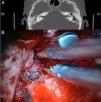

Presentamos los 3 últimos casos tratados mediante abordaje combinado transmastoideo y minicraneotomía, y cierre con cartílago y pericondrio conchal.

We reviewed the last 3 cases treated with combined approach (transmastoid plus minicraniotomy) with 2-layer closure.